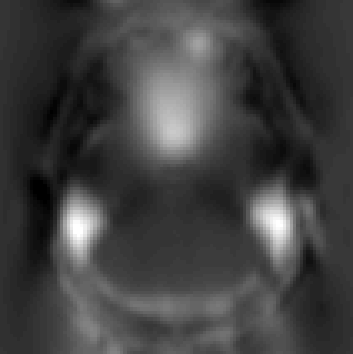

We next take a look at my_field.nii.gz (the output from --fout) to see what topup thinks the off-resonance field looks like.

which has been scaled so that black corresponds to -50Hz and white to 150Hz. This looks like a reasonable off-resonance field with higher than "expected" field above the ear-canals and the roof of the sinuses.